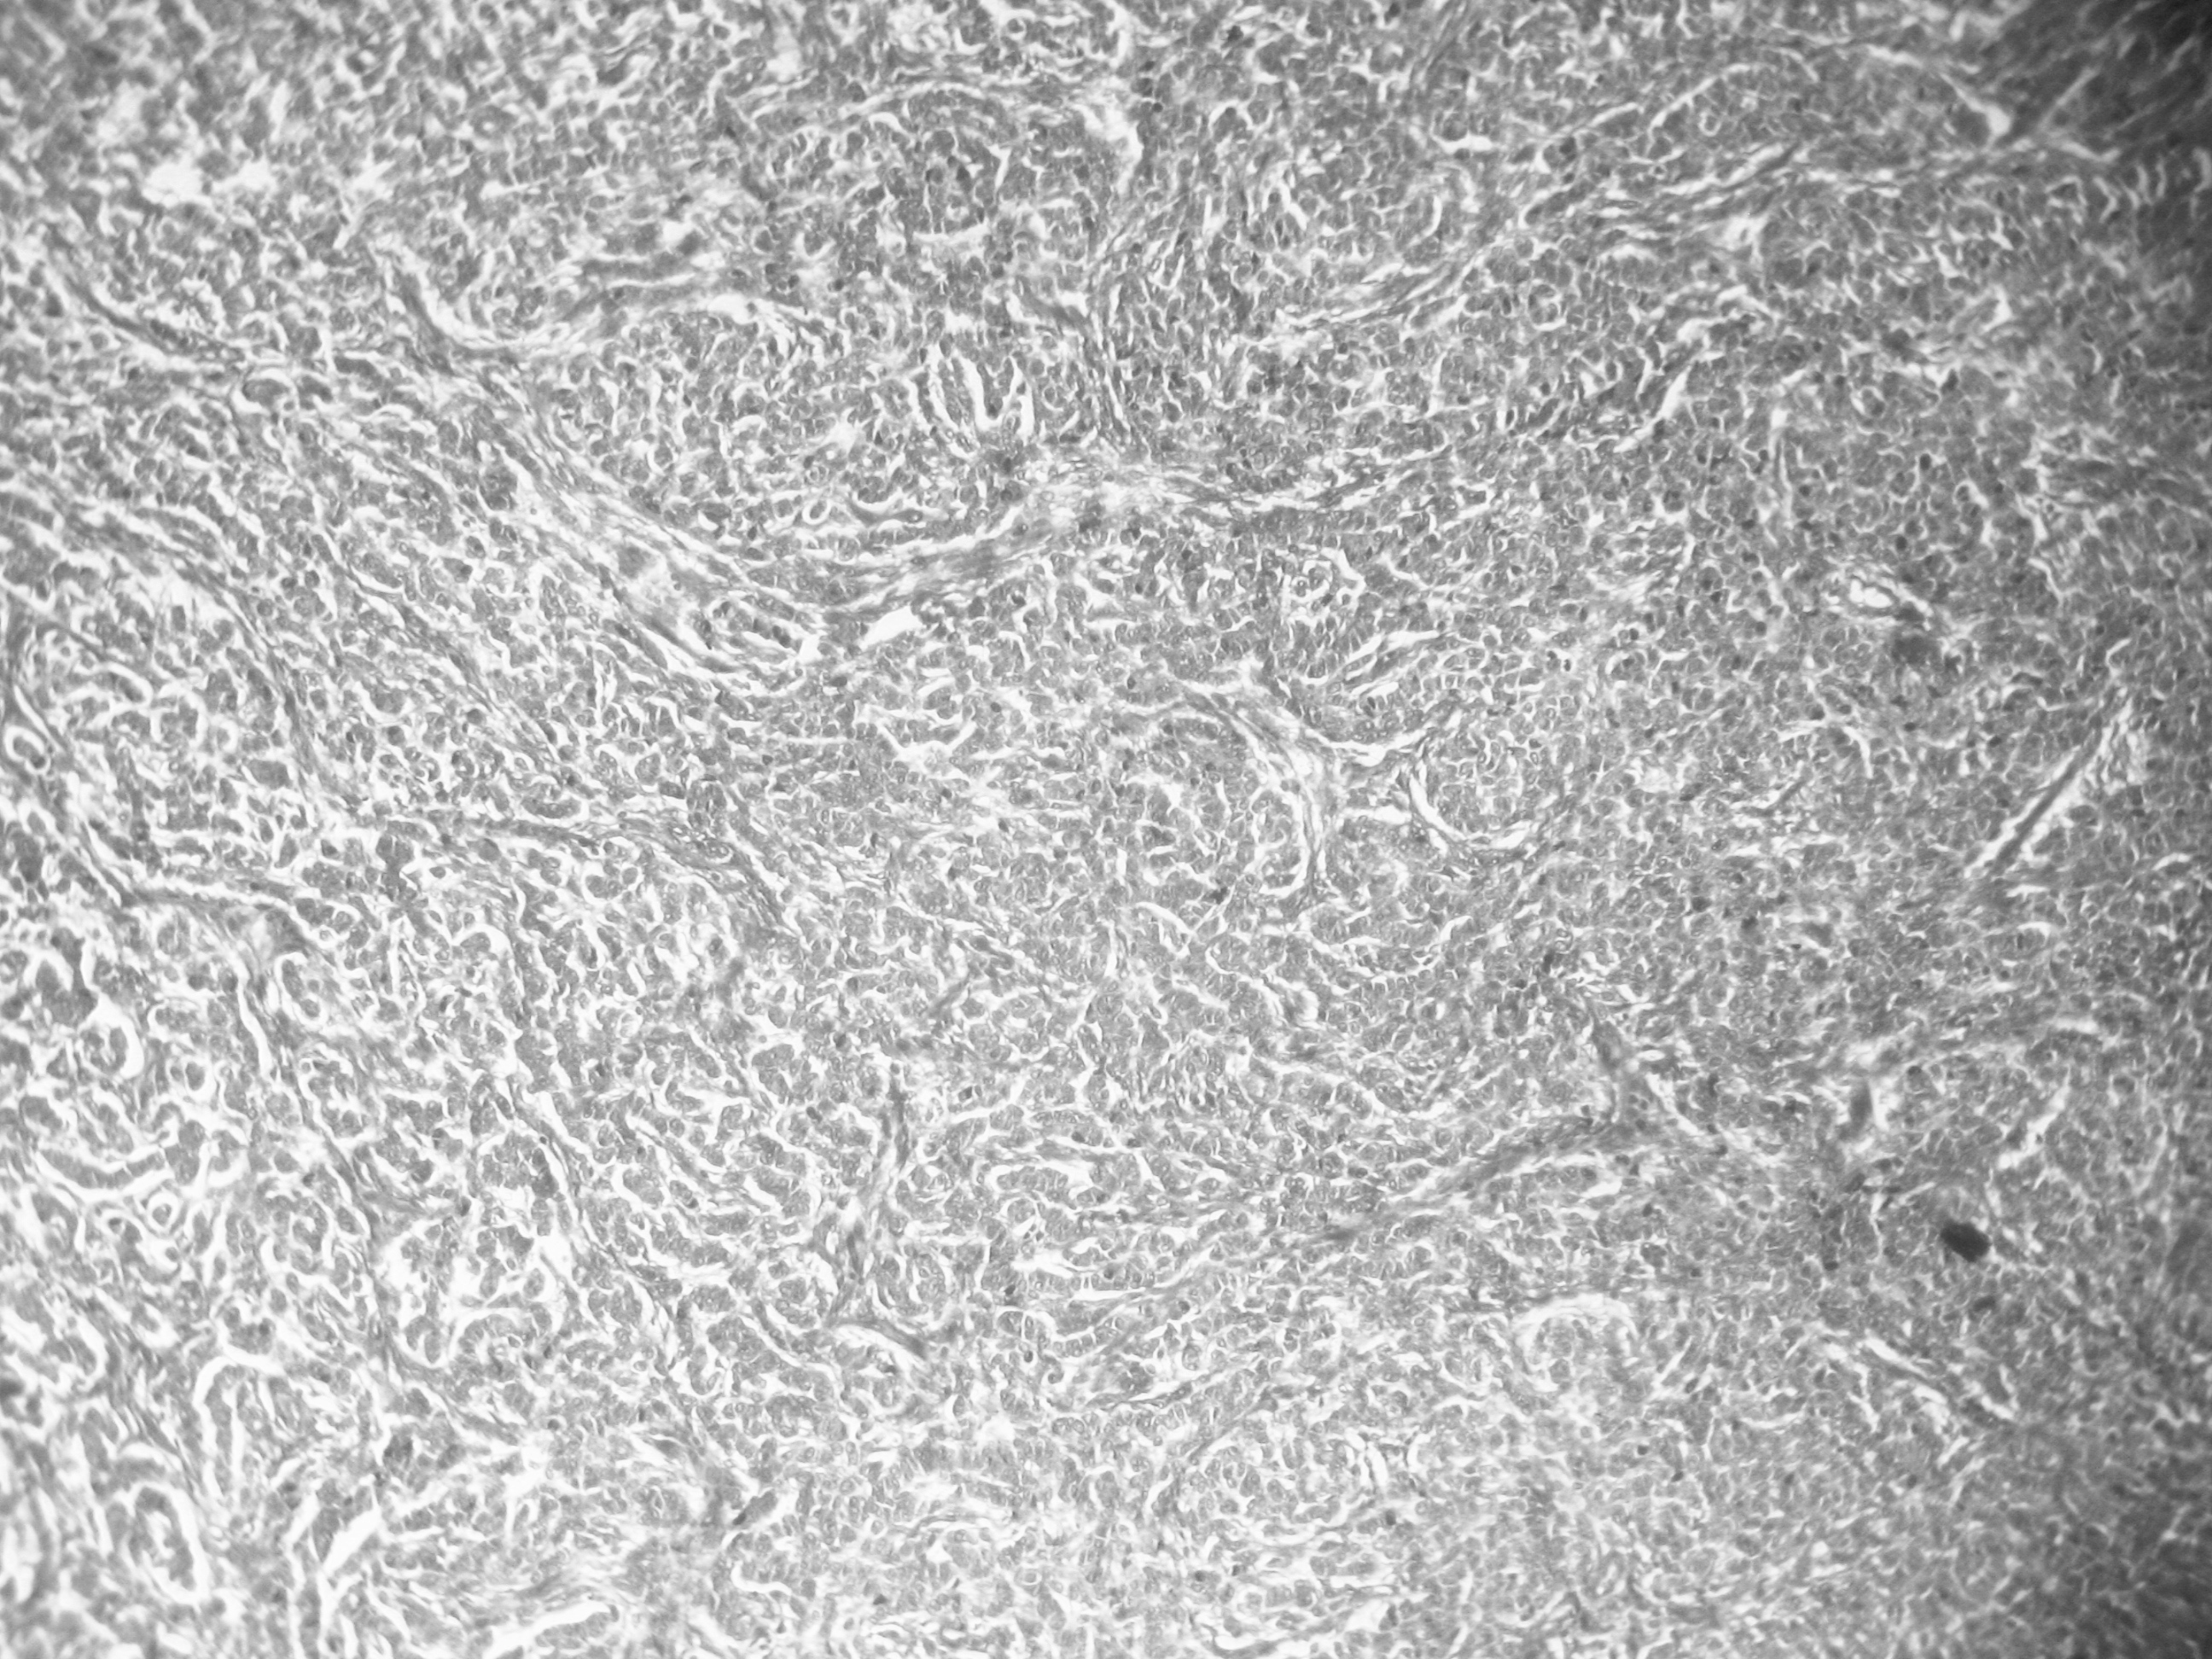

Results: A total 52 ovarian tumors were included in this study. Most common histological types were surface epithelial tumors (92.3%), out of which 54.2% were benign, 41.7% were malignant and 4.2% were borderline. Serous cystadenoma was the most common benign tumor and serous cystadenocarcinoma was the commonest malignant tumor. Abdominal discomfort was the commonest presenting symptom both in benign and malignant tumors (85.7% and 45.4% respectively). Most of the malignant tumors were presented in stage III (50%), followed by stage II (27.3%).